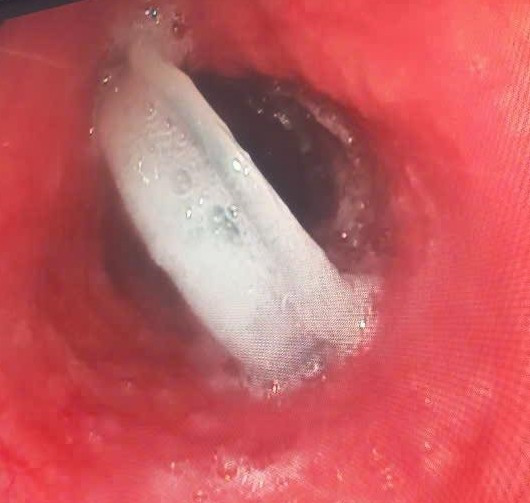

Trước đó, trong lúc uống nước, bệnh nhân vô tình nuốt cả chiếc nắp chai nhựa. Ông cảm thấy khó chịu vùng bụng và được người nhà đưa đến Trung tâm Y tế Nam Đàn. Các bác sĩ đã tiến hành nội soi gây mê và gắp ra thành công dị vật là nắp chai nhựa có đường kính 2,5cm. Sau can thiệp, bệnh nhân ổn định sức khỏe và được xuất viện trong ngày.

Các bác sĩ đã nhanh chóng nội soi, gắp dị vật là nắp chai ra ngoài - Ảnh SKĐS